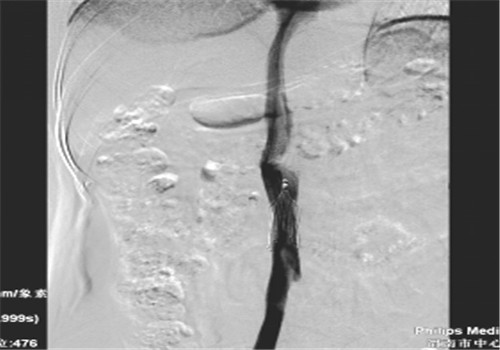

8月中旬患者来院复查,顺利骨取出科钢板,右下肢未见深静脉血栓,于8月14日行下腔静脉滤器取出术,手术顺利,历时30分钟。

据介入科李建国主任介绍,患者血管介入治疗采用了新型的可回收滤器,是目前最新的治疗手段,有着无可比拟的优势,减少肺栓塞猝死并发症的同时、解决了患者终生服用抗凝药的烦恼,亦避免了滤器长期置入体内而出现的并发症。此项手术的成功实施可使渭南区域内广大深静脉血栓患者终生受益。